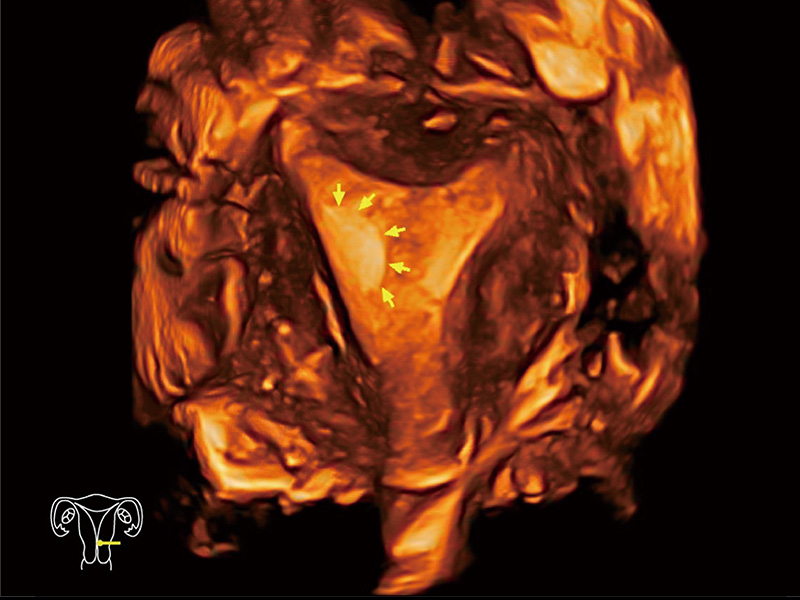

“生育问题”即关系民族复兴,也关系亿万家庭的幸福。随着婚育年龄推迟、社会压力增加等因素,越来越多人群也面临着“生不出、生不好”的问题。辅助生殖作为治疗不孕不育最有效的方法之一,也逐渐成为育儿新希望。而超声检查能为生殖需求人群的初诊评估提供宝贵的信息。 P20 Elite是db真人体育官网匠心打造的一款生殖应用型彩超。她继承db真人体育官网高端极光平台,突破性地将多款新型芯片及硬件模块进行整合,均衡了高端系统性能与小巧灵动机身。P20 Elite卓越的图像质量搭载专科探头,旨在为您提供全面的辅助生殖解决方案。

P20 Elite配备了丰富的生殖探头群和临床应用功能,在卵泡监测、穿刺取卵、胚胎移植、妊娠确认等领域,为生殖需求人群提供了新的临床机会,重新定义高端超声如何应用于生殖健康检查。